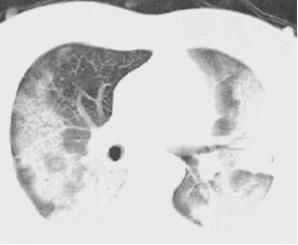

5.平素体健,诉活动后气促数月,CT如下:

也是蝶羽征,心衰临床表现依据不充分,怎么办?

事实证明,蝶翼征+活动后气促,不一定都可以诊断心源性肺水肿!

6.平素体健,活动后稍感气促,CT如下:

这个比较老实,虽然用蝶翼征伪装,但是漏出铺路石征的狐狸尾巴!

很明显,心源性肺水肿依据不足。

最终诊断:PAP:肺泡蛋白沉着症。